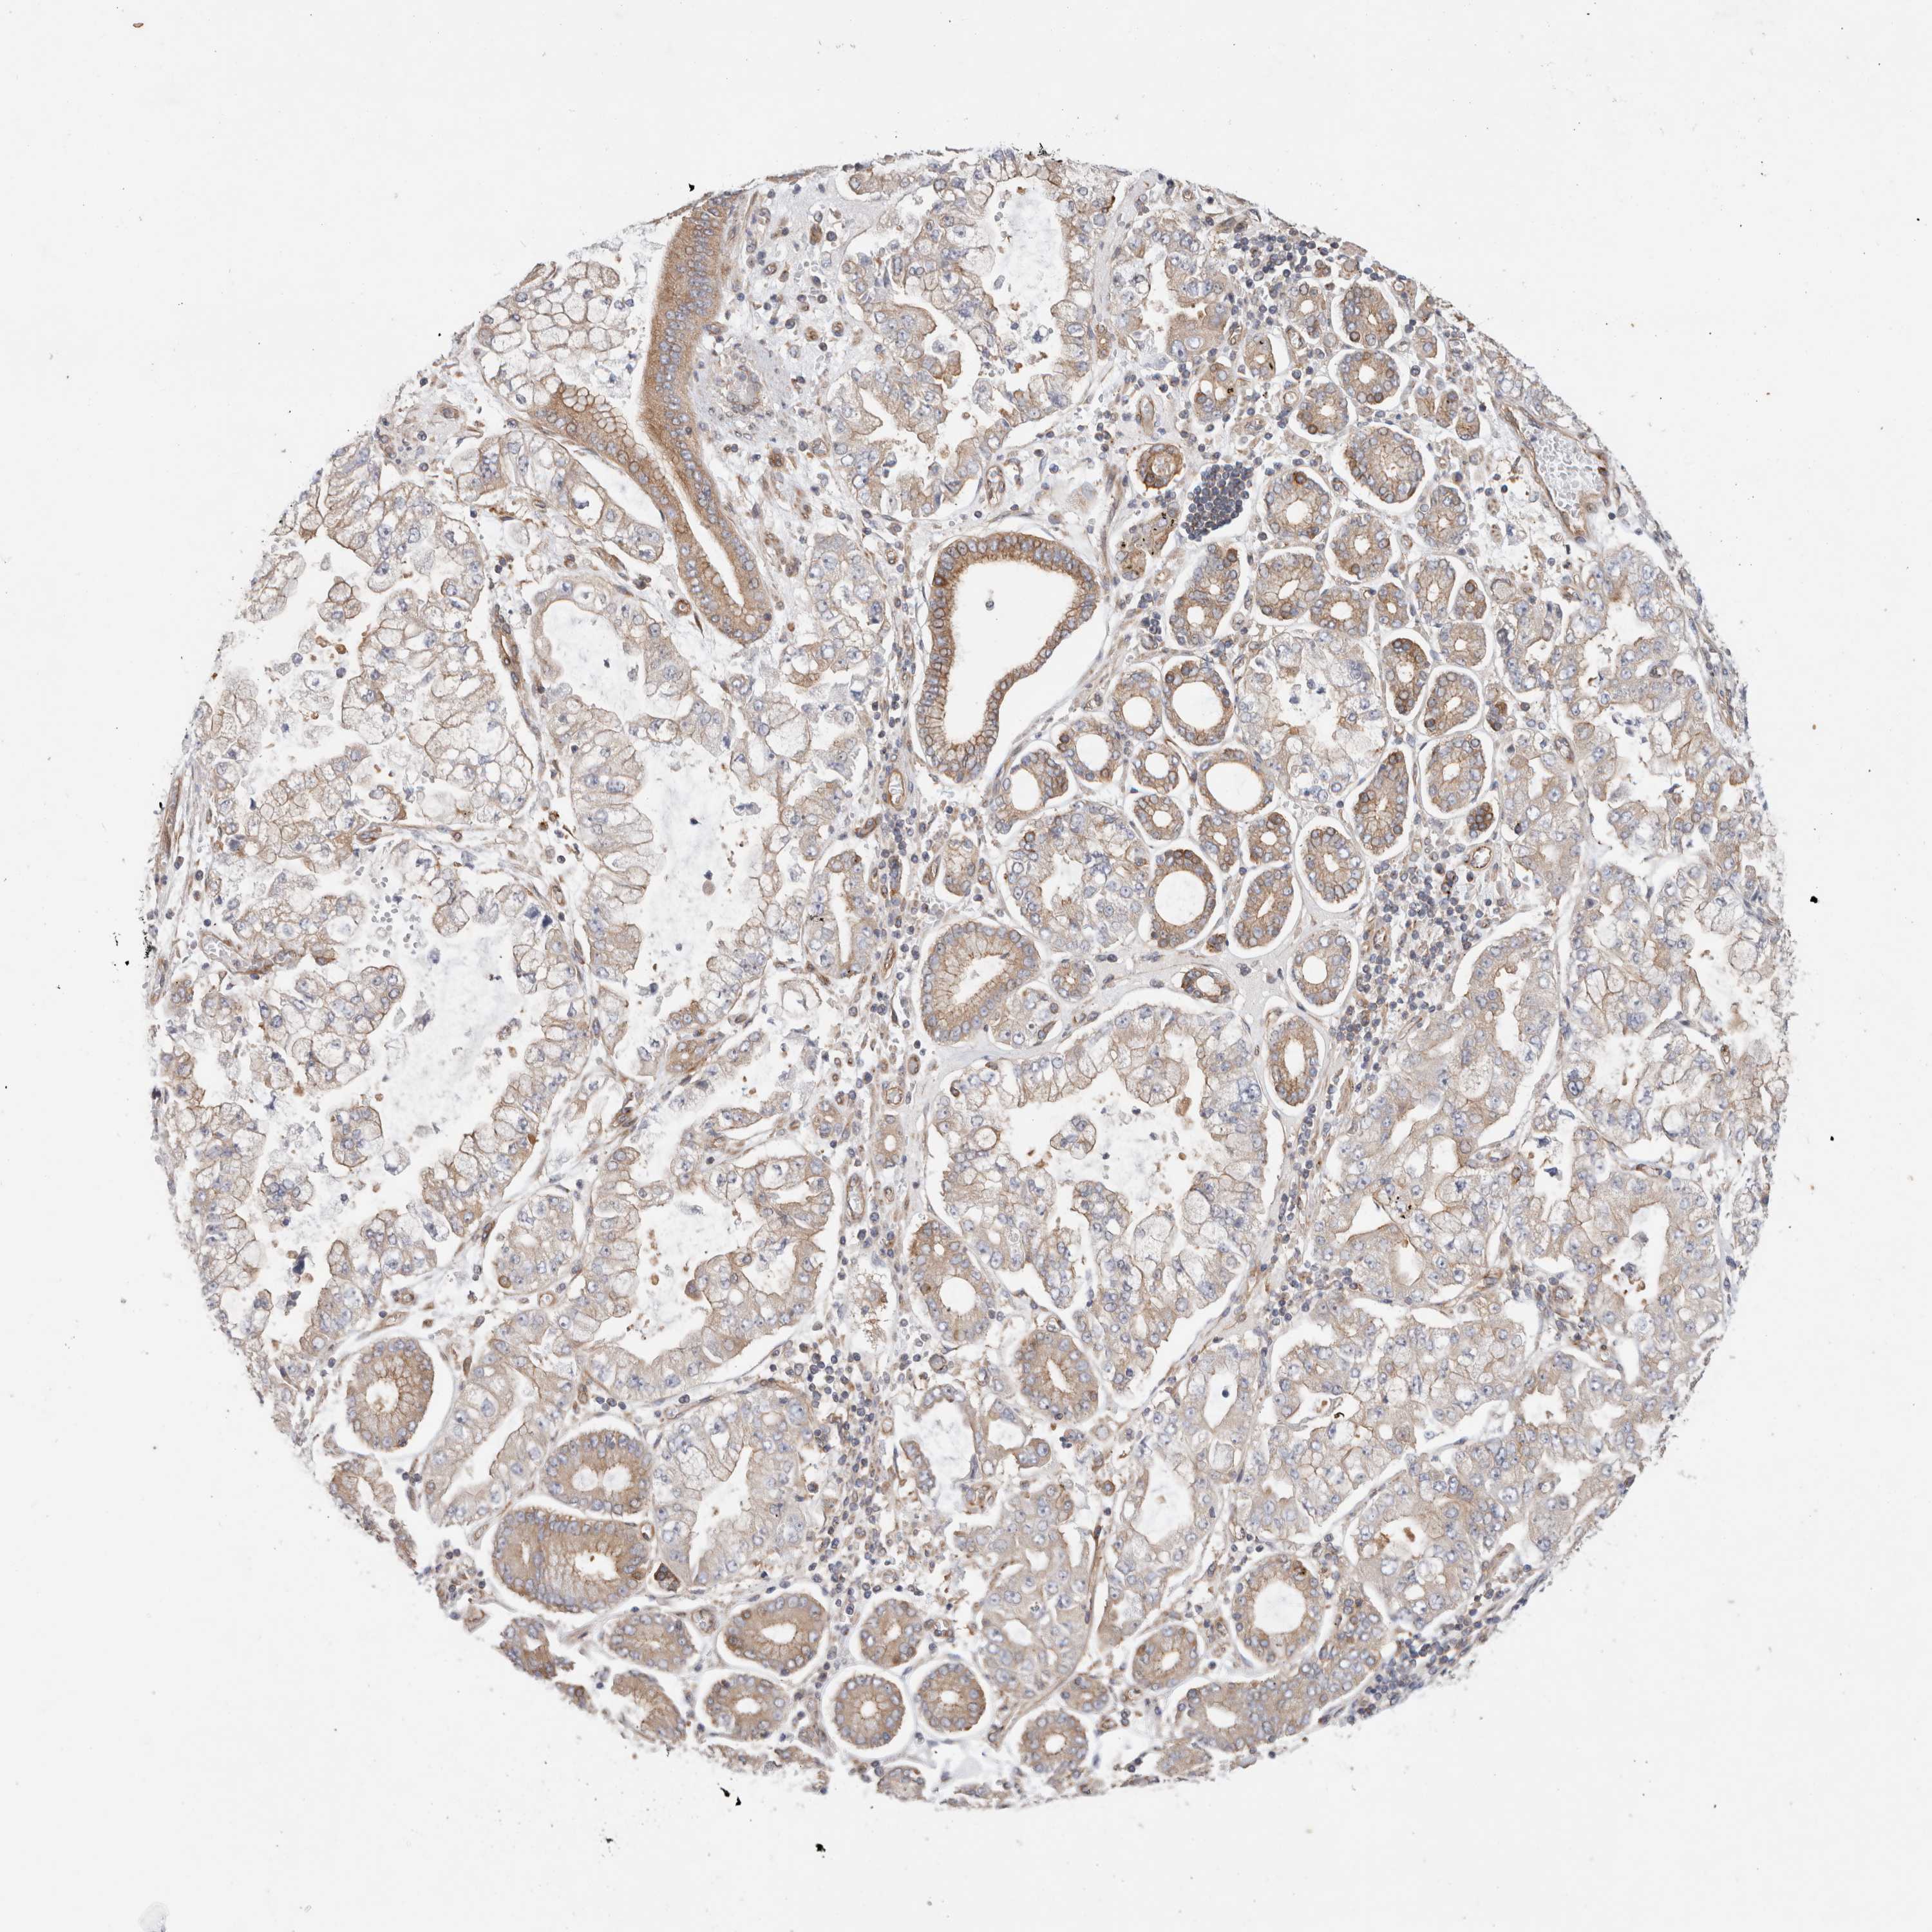

STOMACH CANCER - Protein expressioni

A mouse-over function shows sample information and annotation data. Click on an image to view it in a full screen mode. Samples can be filtered based on level of antibody staining by selecting one or several of the following categories: high, medium, low and not detected. The assay and annotation is described here.

Note that samples used for immunohistochemistry by the Human Protein Atlas do not correspond to samples in the TCGA dataset.

Antibody stainingi

Antibody staining in the annotated cell types in the current human tissue is reported as not detected, low, medium, or high, based on conventional immunohistochemistry profiling in selected tissues. This score is based on the combination of the staining intensity and fraction of stained cells.

Each image is clickable and will lead to virtual microscopy that enables deeper exploration of all samples and also displays staining intensity scores, fraction scores and subcellular localization as well as patient and tissue information for each sample.

Antibody HPA026635

Staining

High

Medium

Low

Not detected

Intensity

Strong

Moderate

Weak

Negative

Quantity

>75%

75%-25%

<25%

None

Location

Nuclear

Cytoplasmic/membranous

Cytoplasmic/membranous,nuclear

Adenocarcinoma, NOS